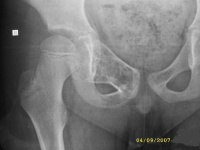

1.好发于4-20岁,多见于5-15岁儿童,少见于成人。好发于股骨颈、股骨上端和肱骨上端。随着年龄增长,囊肿逐渐向骨干方向移动。

3.X线摄片显示长骨干腄端或骨干部位有椭圆形溶骨破坏,边界清楚,其周围可见薄层硬化带,骨皮质可有轻度膨胀变薄。

X线表现病损为界限清楚的射线透亮区,外有一薄层骨硬化边缘,由于囊肿膨胀性生长,造成骨皮质不规则变薄,X线片常呈假分叶状表现,尤多做囊肿在肱骨或股骨的干骺端向下扩展至骨干,向上扩展虽接近骨骺,但后者可被累及,病理性骨折很常见,囊肿可有骨嵴假象,病理检查见病损为单房的囊腔,其中充满清液,囊内衬以薄层纤维组织,骨折后腔内含血性液体并出现骨痂。

X线平片位于长骨干骺端,呈圆形、卵圆形或柱形,沿长骨纵轴发展,表现为轻度膨胀性生长,局部骨皮质变薄,边缘光整,无骨膜增生。合并病理骨折时,骨碎片向囊内移位,称“碎片陷落征”,有助于鉴别。

临床资料A组是待病理性骨折愈合后再治疗骨囊肿,共48例,年龄为6-43岁间;男39例,女9例。肱骨上端20例,肱骨中段6例,股骨上端9例其中(5例髋内翻),远端3例,股骨

颈2例,桡骨远端2例,尺骨远端1例,胫骨上端4例,腓骨头1例。B组是囊肿及骨折一并治疗,共6例,男5例,女1例。肱骨3例,股骨上端1例,股骨颈2例。

主要通过X线片及病理来诊断。X线片示,多发生于长管状骨的干骺端,髓腔中心呈圆形或卵圆形的透光区,边缘清晰而硬化,长轴与骨的长轴一致,多呈中心性生长,无骨膜反应,可见一锐利透光线横过骨病损区。病理:囊内可有少量黄色或血性稀薄液体,囊肿壁内衬一薄层纤维组织,囊内可有骨嵴分隔。镜下见囊壁由成纤维细胞多核细胞胶原纤维构成。